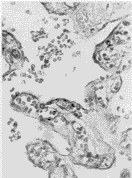

2.2 iNOS mRNA原位杂交

正常妊娠组多数胎盘合体滋养层细胞几乎无着色或仅有少许着色;妊高征组大多数胎盘的合体滋养层细胞内可见局灶性紫蓝色着色增加,说明妊高征胎盘合体滋养层细胞内iNOS mRNA的表达增加(图7、8),两组胎盘的血管平滑肌细胞均见较明显着色。

图7 正常妊娠胎盘,合体滋养层细胞内未见iNOS mRNA表达。 ISH×400

Figure 7 Normotensive placenta, there is no iNOS mRNA expression in syncytiotrophoblast. ISH ×400

图8 妊高征胎盘,合体滋养层细胞内可见iNOS mRNA表达。 ISH×400

Figure 8 Preeclampsia placenta, there is stronger iNOS mRNA expression in syncytiotrophoblast. ISH ×400